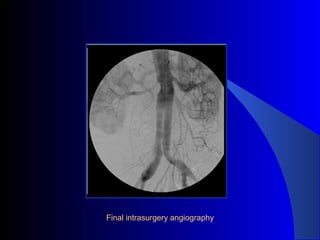

The document discusses the clinical application of the Endurant stent graft system in treating aorto-bisiliac aneurysms, detailing procedures performed on two male patients aged 72 and 73. Each patient had a history of dyslipidemia and carotid atherosclerosis, with procedures involving the bilateral bell bottom technique and the use of coils and fibrin glue. It includes pre-surgery imaging, intrasurgery angiography, and follow-up control scans to monitor outcomes.